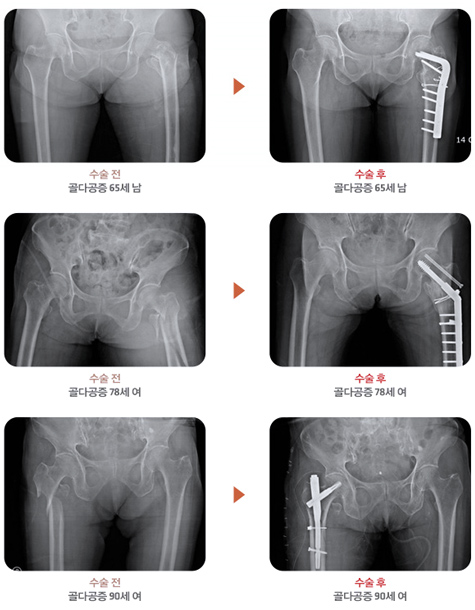

°¡Àå ¹®Á¦°¡ ¸¹ÀÌ µÇ´Â °í°üÀýºÎ(¾ûµ¢ÀÌ) °ñÀýÀÇ ÀÓ»óÀû ¿¹

°í°üÀýºÎ(¾ûµ¢ÀÌ) °ñÀý Ä¡·á À̹ÌÁö

¾çµ¿Çö Á¤Çü¿Ü°ú Àü¹®ÀÇ